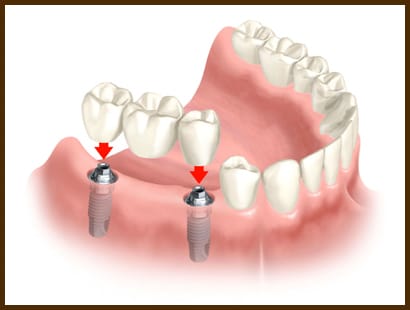

Mentinerea anatomiei : Daca aveti dinti lipsa, osul in care au fost implantati acestia se va atrofia in timp. Oasele maxialre atrofiate dau aspectul de imbatranire prematura si duc la pierderea structurii faciale. Implantele dentare pot ajuta la prevenirea deteriorarii maxilarelor astfel incat fata sa-si pastreze structura naturala.[/fusion_text][/fusion_builder_column][fusion_builder_column type=”1_2″ last=”yes” spacing=”yes” background_color=”” background_image=”” background_repeat=”no-repeat” background_position=”left top” border_size=”0px” border_color=”” border_style=”” padding=”” class=”” id=””][fusion_title size=”3″ content_align=”left” style_type=”double solid” sep_color=”” class=”” id=””]Diferente cu/fara implante dentare[/fusion_title][fusion_accordion class=”” id=””][fusion_toggle title=”Pastreaza dintii sanatosi” open=”no”]Alternativa clasica la un dinte lipsa este o punte dentara. Aceasta presupune slefuirea dintilor invecinati dintelui lipsa. Prin folosirea unui implant dentar dintii naturali raman integrii.[/fusion_toggle][fusion_toggle title=”Permit lucrari fixe” open=”no”]In stomatologia clasica este nevoie de dinti stalpi pentru a ancora o punte dentara. Atunci cand nu exista dinti care sa fie folositi ca stalpi distali (situati posterior) lipsa dintilor se numeste edentatie terminala. Stomatologia clasica rezolva aceasta problema prin aplicarea unor lucrari mobilizabile („proteze”) (care se indeparteaza de catre pacient pentru igienizare).[/fusion_toggle][/fusion_accordion][/fusion_builder_column][/fusion_builder_row][/fusion_builder_container][fusion_builder_container backgroundcolor=”” backgroundimage=”” backgroundrepeat=”no-repeat” backgroundposition=”left top” backgroundattachment=”scroll” video_webm=”” video_mp4=”” video_ogv=”” video_preview_image=”” overlay_color=”” overlay_opacity=”0.5″ video_mute=”yes” video_loop=”yes” fade=”no” bordersize=”0px” bordercolor=”” borderstyle=”” paddingtop=”20px” paddingbottom=”20px” paddingleft=”0px” paddingright=”0px” menu_anchor=”” equal_height_columns=”no” hundred_percent=”no” class=”” id=””][fusion_builder_row][fusion_builder_column type=”1_1″ background_position=”left top” background_color=”” border_size=”” border_color=”” border_style=”solid” spacing=”yes” background_image=”” background_repeat=”no-repeat” padding=”” margin_top=”0px” margin_bottom=”0px” class=”” id=”” animation_type=”” animation_speed=”0.3″ animation_direction=”left” hide_on_mobile=”no” center_content=”no” min_height=”none”][fusion_title size=”3″ content_align=”left” style_type=”double solid” sep_color=”” class=”” id=””]Avantaje[/fusion_title][fusion_text]Iata astfel in cateva cuvinte si mai ales imagini avantajele tratamentului prin implante.[/fusion_text][/fusion_builder_column][fusion_builder_column type=”1_1″ background_position=”left top” background_color=”” border_size=”” border_color=”” border_style=”solid” spacing=”yes” background_image=”” background_repeat=”no-repeat” padding=”” margin_top=”0px” margin_bottom=”0px” class=”” id=”” animation_type=”” animation_speed=”0.3″ animation_direction=”left” hide_on_mobile=”no” center_content=”no” min_height=”none”][fusion_tabs design=”classic” layout=”horizontal” justified=”yes” backgroundcolor=”” inactivecolor=”” bordercolor=”” class=”” id=””][fusion_tab title=”Varianta 1″ icon=”fa-share”]

Implantele dentare permit lucrari fixe pe aceste zone de edentatii terminale si totodata reducerea costurilor (protezele complexe necesita mai multi dinti pe care sa se ancoreze cu sisteme speciale.